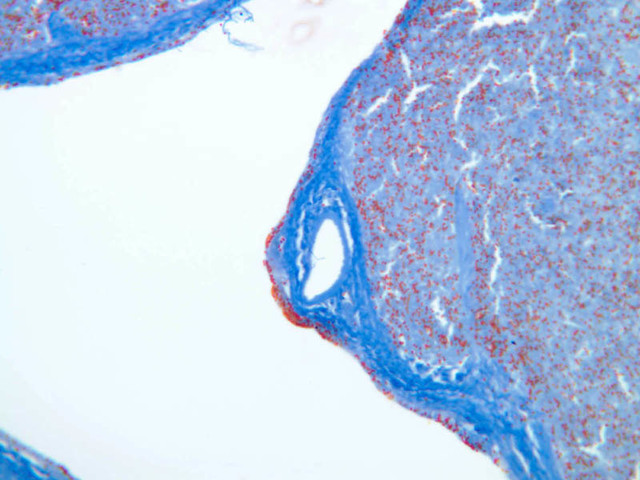

Sections through the spleen (slides A-36, aniline blue [2.5x, 10x, 20x-labeled, 40x] [2.5x, 10x-labeled, 20x-labeled, 40x]; A-37, retic [2.5x, 10x, 20x-labeled, 40x]; A- 37, H&E [2.5x-labeled, 10x, 20x, 40x]; A-38, H&E [10x, 20x, 40x]; A-39, H&E [2.5x, 10x, 20x, 40x]) show a thick investing capsule composed of collagenous tissue and smooth muscle, typically covered with mesothelium. In slide A-36 muscle and collagen are brightly stained. The capsule and mesothelium completely surround the organ and the fibrous portion enters the splenic substance at the hilus around the splenic arteries and veins forming trabeculae of fibromuscular tissue within the splenic substance. This fibromuscular tissue enables the spleen to expel blood by contracting. Identify trabeculae as fibrous partitions in the section and look for blood vessels within them.

Where the trabecular arteries pass into the splenic pulp, they become invested by a sleeve of lymphoid tissue. This lymphatic tissue collectively forms the white pulp of the spleen (A-36 [2.5x, 10x, 20x, 40x]). It also is referred to as the periarterial lymphatic sheath or PALS. On an H&E stained section (A-38 [2.5x, 10x, 20x, 40x] [2.5x, 10x, 20x, 40x]) the white pulp will appear as basophilic clumps of lymphoid cells. The arteries of the white pulp are called central arteries, although they may be displaced to one side of the lymphoid sleeve by the presence of a nodule. The majority of cells forming the PALS are T lymphocytes. In places the covering of lymphatic tissue is enlarged due to the presence of lymphoid nodules (splenic or Malphighian corpuscles) which are comprised predominantly of B lymphocytes.

The remainder of the cellular mass in the spleen is red pulp (A-38 [10x, 20x, 40x]), made up of red and white cells of the blood enmeshed in the reticular tissue of splenic cords and present in the splenic sinuses. After passing through the PALS, the trabecular arteries branch to form smaller arterial vessels known as penicillar arterioles which narrow, forming arterial capillaries that empty into the cords of the red pulp (open circulation) or into the venous sinuses (closed circulation). In the splenic sinuses the cells of the blood are exposed to red pulp macrophages. The splenic sinuses eventually become confluent to form veins that enter the trabeculae and gradually merge meeting in the hilus to form splenic veins.

Examine the composition of the red pulp tissue. The three dimensional structure of the red pulp is analogous to Swiss cheese with the holes being the venous sinuses and the cheese being the parenchyma (i.e. splenic cords). On slide A-36 which is stained with Mallory's aniline blue locate examples of the splenic sinuses ([2.5x, 10x, 20x, 40x-labeled] [10x, 20x, 40x]). The walls of the splenic sinuses consist of adjoining specialized endothelial cells whose nuclei in many cases stand out from the wall in a bead-like fashion. The basement membrane of the epithelial cells stains blue revealing the sinuses quite nicely. Usually the sinus lumen is filled with red cells and leukocytes. The skeletal framework of the cords is provided by a network of reticular fibers. As above, the reticular cells are best seen using a reticular fiber stain (slide A-37 [2.5x, 10x, 20x, 40x-labeled]). Look for the large pale nuclei of reticular cells that have darkly stained reticular fibers. Fibers run irregularly in the cords, but clearly outline the sinuses around which they are wrapped. Notice on this same slide that there is much less reticular tissue in the white pulp than the red. The splenic cords occur around the sinuses and are distinguished by the presence of disintegrating red blood cells undergoing phagocytosis.